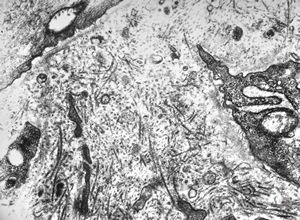

M,6y. | Alport syndrome- digital photo from the screen